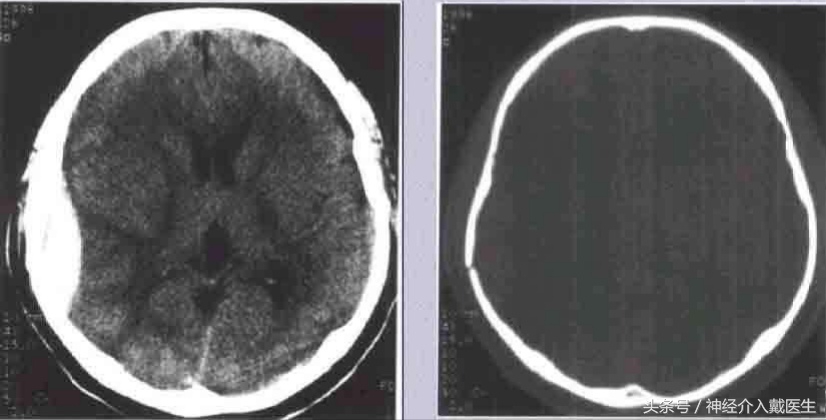

儿童生长性骨折:好发于额顶部,为小儿颅盖线形骨折中的特殊类型,婴幼儿多见。一般认为小儿硬脑膜较薄且与颅骨内板贴附较紧,当颅骨发生骨折裂缝较宽时,硬脑膜亦常同时撕裂、分离,以致局部脑组织、软脑膜及蛛网膜突向骨折的裂隙。由于脑搏动的长期不断冲击,使骨折裂缝逐渐加宽,以致脑组织继续突出,最终形成局部搏动性囊性脑膨出,病儿常伴发癫痛或局限性神经废损。治疗原则以早期手术修补硬脑膜缺损为妥。 凹陷骨折多见于额、顶部,常为接触面较小的钝器打击或头颅碰撞在凸出的物体上所致。着力点头皮往往有擦伤、挫伤或挫裂伤。颅骨大多全层陷入颅内,偶尔仅为内板破裂下凹。一般单纯凹陷骨折,头皮完整,不伴有脑损伤多为闭合性损伤,但粉碎凹陷骨折则常伴有硬脑膜和脑组织损伤,甚至引起颅内出血。

( 1 )闭合性凹陷骨折 儿童较多,尤其是婴幼儿颅骨弹性较好,钝性的致伤物,可引起颅骨凹陷,但头皮完整无损,类似乒乓球样凹陷,亦元明显的骨折线可见。患儿多无神经机能障碍,无需手术治疗。如果凹陷区较大较深,或有脑受压症状和体征时,可于凹陷旁钻孔,谨慎经硬膜外放入骨撬,将陷入之骨片撬起复位。术后应密切观察以防出血。

成年人单纯凹陷骨折,如果面积大于 5cm,或者直径,深度超过 lcm ,或者伴有神经缺损症状和体征,需要手术治疗。